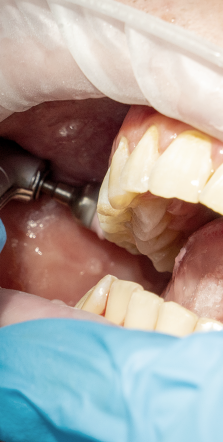

첫번째 치은염 증상은 바로

잇몸의 붓기와 출혈이였어요.

평소 치실로 꼼꼼하게 양치를

해주시는 분들의 경우 잇몸에서

피가 나는 것은 흔한 현상이지만

이러한 증세가 지속적으로 자주

발생한다면 이는 치은염으로 인한

현상은 아닌지 의심해보셔야 했어요.

두번째 증상은 잇몸이 붉게 변하며

붓기가 생기는것인데요.

건강한 잇몸은 연분홍색을 띄며,

잇몸에 염증이 발생하면 빨갛게

부워오르게 된다고 했어요.

이러한 경우 잇몸이 예민해져 있어

살짝만 칫솔로 건드려도 출혈이 쉽게

발생하며 통증 또한 느껴질 수 있는

부정적인 상태에 해당됐어요.